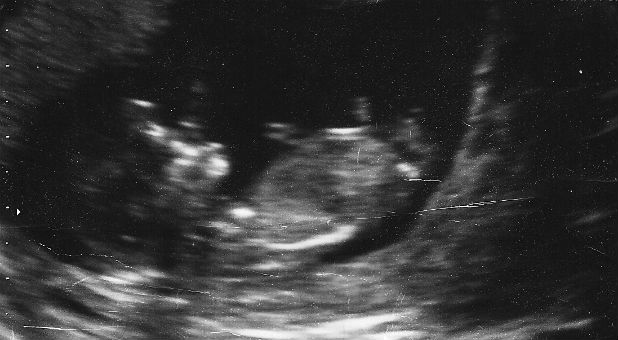

There is a reason many women contemplating abortion decide not to abort when they see an ultrasound of their baby. There is no denying the humanity of this tiny creature, which is anything but a clump of cells.

As the baby grows in the womb and is seen by ultrasound imaging, it’s common to hear parents exclaim, “Look at those little hands! Look at that adorable nose (it looks like Grandpa’s nose, doesn’t it?)! And look—it’s a girl!” (Or, “It’s a boy!”)

How amazing it is to see the ultrasound of your baby, especially when it’s your first child. Not surprisingly, both of our daughters, now in their late 30s, had the identical reaction when they saw the ultrasounds of their first babies: How could anyone abort their child?

It is hard to deny the personhood of the fetus when you see an ultrasound, which is why, during last year’s Super Bowl, Doritos incurred the wrath of NARAL (the National Abortion Rights Action League) when it aired an innocent, light-hearted, commercial featuring a very pregnant woman, her husband and an ultrasound of their baby. According to NARAL, Doritos had committed the cardinal sin of “humanizing fetuses.” Oh, the very thought of it!

But it is not just the fetal heartbeat that holds no meaning for Weigel. Ultrasounds also have no meaning for her since … well, since she’s doesn’t believe they should. (If you think I’m exaggerating, read her article.) She notes that posting pictures of ultrasounds on social media has “heightened the social reality of the unborn,” as if this were somehow a bad, misleading thing.

And she points to an American couple who “posted a video of their sonogram fast-forwarded so that their fetus appeared to be clapping in time as they sang, ‘When You’re Happy and You Know It, Clap Your Hands.'” The implication is that because the video was sped up, giving the false impression that the baby was clapping to the beat, the more basic impression was also false, namely that there was a little human being in that mother’s womb who was putting their two little hands together. Pretty good for a clump of cells and a mass of tissue!

Although Weigel cites those who claim that pregnant women who see their ultrasounds are less likely to abort, she disputes these claims, pointing to a “2014 study published by the journal Obstetrics and Gynecology, which drew on the medical records of nearly 16,000 women seeking abortions” and “found that viewing an ultrasound had a negligible impact on whether they decided to proceed.”